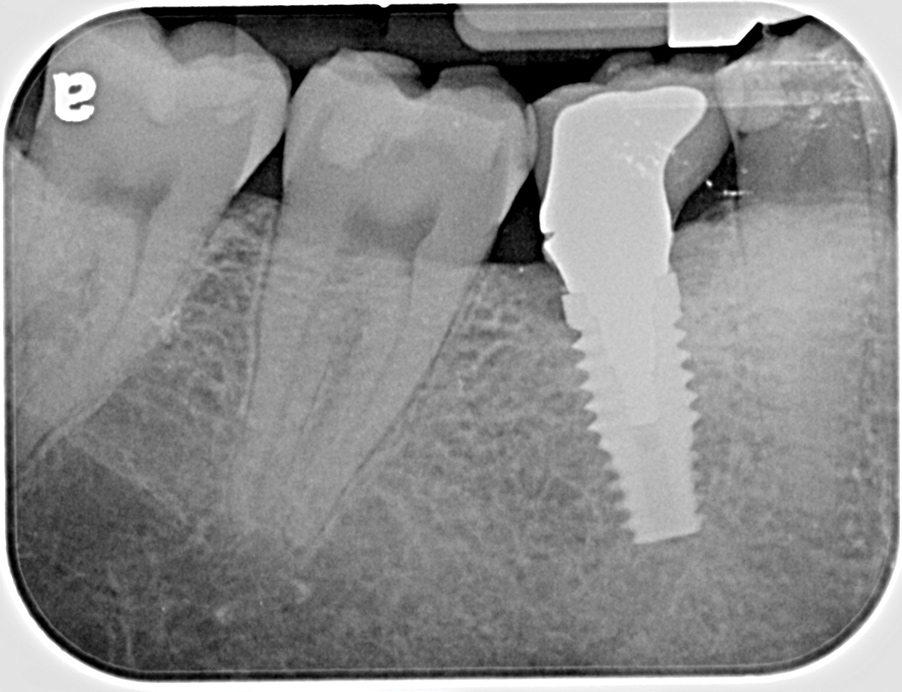

Fig 9. Radiograph depicting fractured screw inside of the implant.

Figure 9